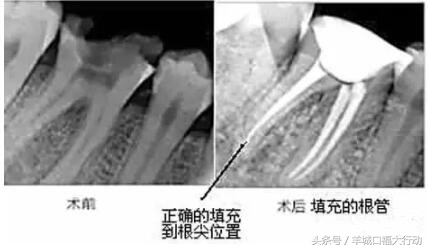

牙齿出现了疼痛,很多情况医生都会建议患者进行根管治疗,也就是老百姓常说的抽神经。其实很多人并不懂牙齿有洞出现了疼痛为什么不能直接补一下,而是非要选择抽神经。其实坦白的讲,如果牙齿出现了剧烈的疼痛,那么意味着患者已经错过了最佳的补牙治疗机会,那么最佳的治疗时机已经错过了,就不得不选择另一种治疗方案,也就是专业上讲到的根管治疗。

另外针针对磨牙来讲,通常磨牙会有3到4个牙根,但是牙根里面的神经可能会有多根,正常的磨牙根管治疗是指治疗3根神经的费用,如果这个牙齿的神经数量超过3根那么每多出来一根就要加收一根神经的费用。